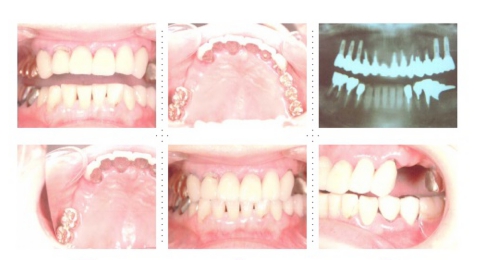

症例4

57才 女性

知人の歯科医からのご紹介。良く噛めない為、元気が出ない。介護の仕事を続けるためにも、歯を治療して自分がもっと元気になりたい。最初は部分的に治療する予定だったのですが、歯のない部分はインプラントを埋入し、最終的には上下顎全ての歯を治療し、しっかりものが噛めるようになりました。